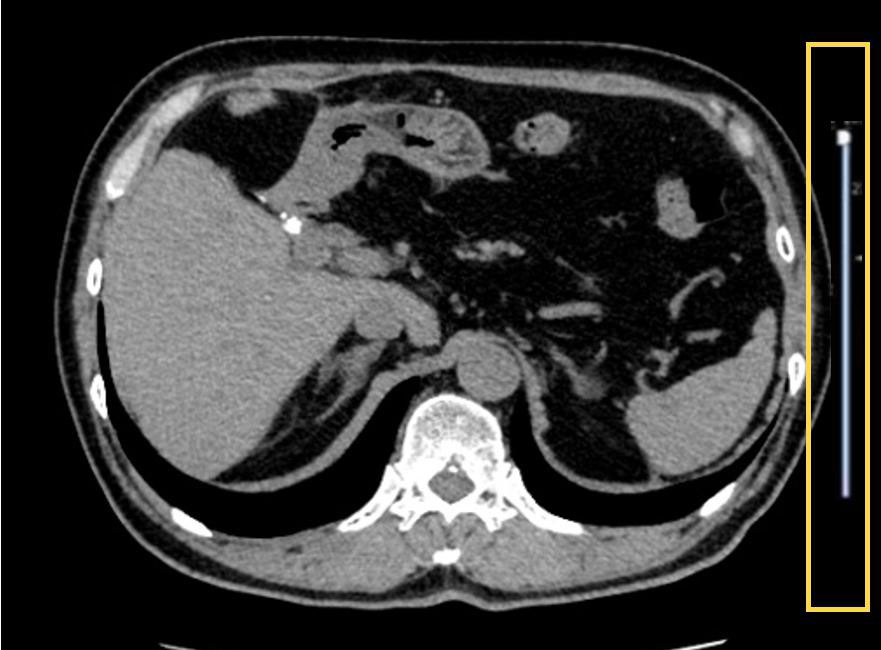

撮影プロトコルの自動調整

Ascendには従来のAEC (Auto Exposure Control)の発展機能であるAuto Prescriptionという機能が搭載されており、スカウト画像からそれぞれの患者様があらかじめ設定したどのサイズに該当するかを判断し、その該当サイズに対するkV、ローテーションタイム、ノイズインデックスなどを自動変更することが可能となっており患者様の体格に関わらず画質のノイズバランスの調整が可能である。この機能により、患者様の体格によってのローテーションタイムの変更が不要となり、撮影パラメーターを気にすることなく安定した画像出力が可能となっている。以前であれば線量不足を気にしてパラメータの確認等が必要だったが、その煩わしさが解消されている。

Ascend_Satodaiichi08.jpg

Fig.7 AIによる撮影プロトコル調整